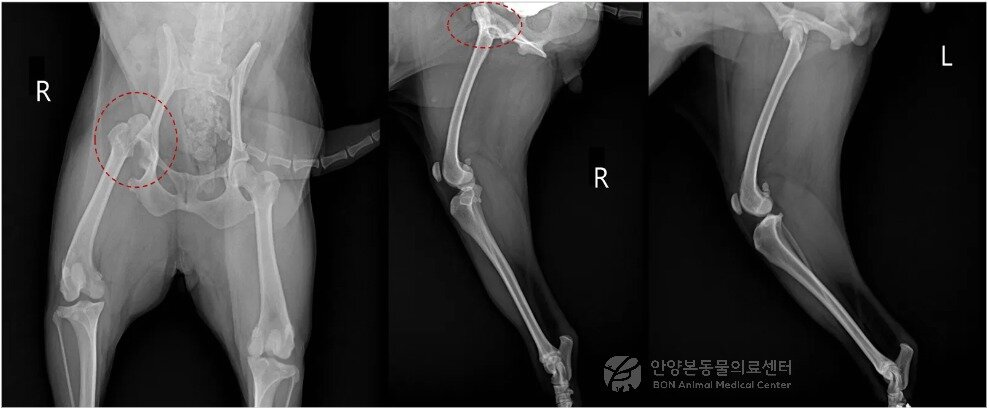

본문 이미지 - 고관절 탈구가 롹인된 반려견의 엑스레이(본동물의료센터 제공) ⓒ 뉴스1

고관절 탈구가 롹인된 반려견의 엑스레이(본동물의료센터 제공) ⓒ 뉴스1